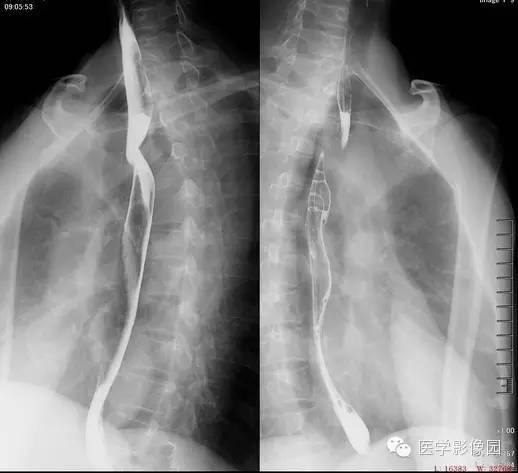

钡餐造影

道上段于主动脉弓上缘以上显示一条由左下向右上方斜行边缘光滑的螺旋形压迹,宽约1CM左右;局部可见血管搏动现象。食道粘膜皱襞规则完整,管壁柔韧度及管腔扩张正常,其以上的食管无明显扩张。